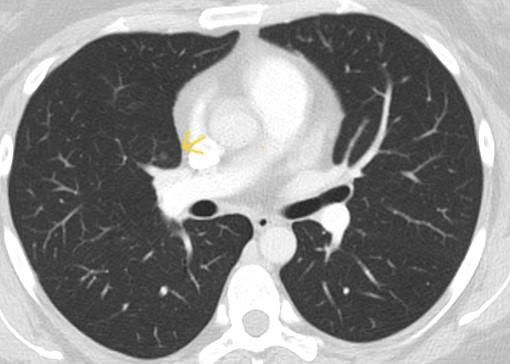

간유리 결절 같나요 고형인가요. 그 외 질문 부탁드려요

*좀더 하얀색인 사진 2장은 24년 조영제 폐CT 이고, 나머지 3장은 25년 저선량 CT사진입니다.

25년에 같은 저선량 CT에서 lucas라는 AI가 찾아낸 사진 2장은 빨간동그라미로 되어있습니다.*

♧ 고형 같나요 간유리 같나요?

Ai 는 우상엽 solid라는데 오늘 2차병원에서 중간위치고 간유리에 가깝다라고 들어서요

solid nodule인지 ground glass nodule인지는 clear cut하게 나누어지는 것이 아닙니다. 결절이 색이 또렷하면 solid nodule인 것이고 흐지부지하면 ground glass nodule인 것입니다. 이건 육안 소견을 두고 말하는 것입니다. 따라서 일부 nodule에 있어서는 판독하는 의사에 따라 소견이 다를 수 있습니다.